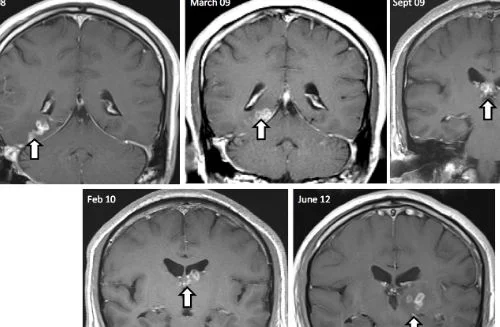

ওই ঘটনায় অস্বাভাবিক পেটে ব্যথা ও কাশির পাশাপাশি রাতে প্রচুর ঘাম এবং ডায়রিয়া হয় ওই নারীর। এর ফলে স্মৃতিভ্রষ্টের ঘটনা ও বিষণ্ণতাও বাড়ছিল। ২০২১ সালের জানুয়ারির শেষে দিকে ওই নারীকে হাসপাতালে ভর্তি করা হয়। পরে মস্তিষ্কে স্ক্যান করলে মগজের ডান ফ্রন্টাল লোবে একটি ক্ষত দেখা যায়। পরের বছরের জুনে বায়োপসি করার সময় তার শারীরিক অসুস্থতার কারণ প্রকাশ পায়। অস্ত্রপচারের পর ওই নারী ধীরে ধীরে সেরে উঠছেন।